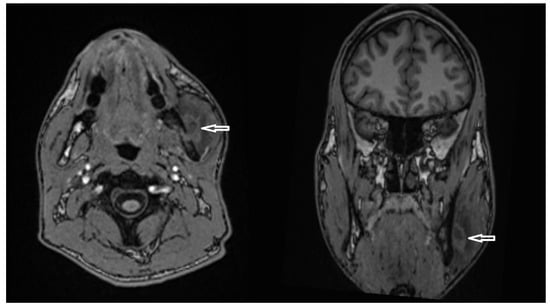

OPG CT/MRI | 13 mm | Incision and drainage of the abscess and surgical curettage | 48 mm |

| 5 | Female | 45 | External auditory canal abscess |

OPG CT/MRI | 10 mm | Incision and drainage of the abscess | 51 mm |